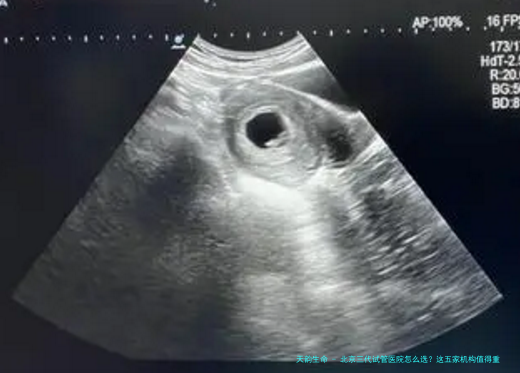

先说个冷知识:北京目前有12家医院具备三代试管资质。根据2023年国家辅助生殖技术质量管理控制中心数据,北医三院以72.3%的临床妊娠率领跑,年接诊量突破3万人次。协和医院生殖中心虽然规模稍小,但针对染色体异常患者的成功案例特别突出,去年完成的一例罗氏易位携带者案例还上了《生殖医学杂志》。